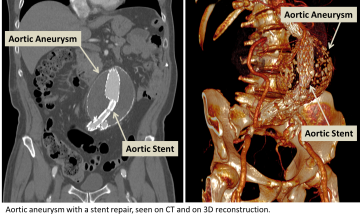

Aortic aneurysm with a stent repair seen on CT and on 3D Reconstruction